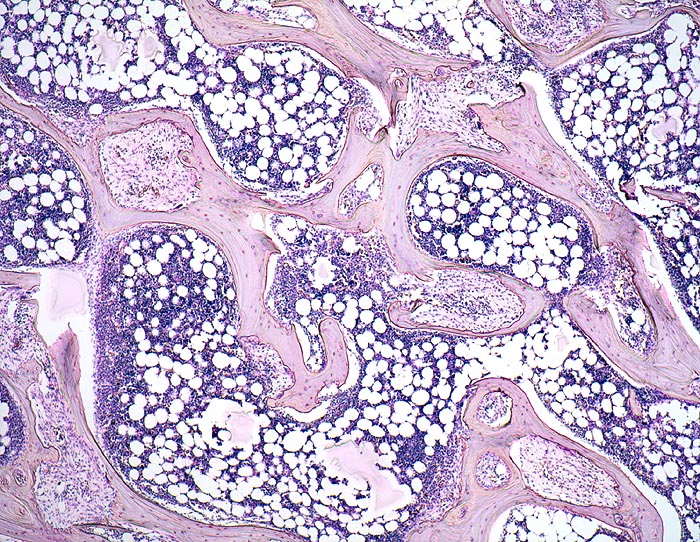

Am häufigsten tritt die Fibroosteoklasie im Rahmen einer renalen Osteopathie bei Dialysepatienten auf und ist dann meist kombiniert mit osteomalazischen (Vitamin D Mangel) und osteoporotischen Veränderungen. Seltener tritt die Fibroosteoklasie im Rahmen eines primären Hyperparathyreoidismus auf (Adenom>Hyperplasie>Karzinom der Nebenschilddrüse).

Histologisch findet sich beim Hyperparathyreoidismus eine gesteigerte Osteoklastentätigkeit mit Tunnellierung der Knochenbälkchen und gleichzeitig eine gesteigerte Knochenneubildung mit Fibrose der peritrabekulären Markräume. Die Maximalvariante eines sogenannten „Braunen Tumors“ -Osteodystrophia fibrosa generalisata cystica von Recklinghausen- kommt heute in Mitteleuropa praktisch nicht mehr vor. Die braune Farbe dieses Tumors wird durch sekundäre Einblutungen und Siderinablagerungen verursacht.

• Dünne Spongiosabälkchen mit herdförmiger peritrabekulärer Fibrose.

• Vermehrte Osteoklastentätigkeit: Spongiosabälkchen mit tiefen Resorptionslakunen, welche die Bälkchen z.T. tunnelartig aushöhlen.